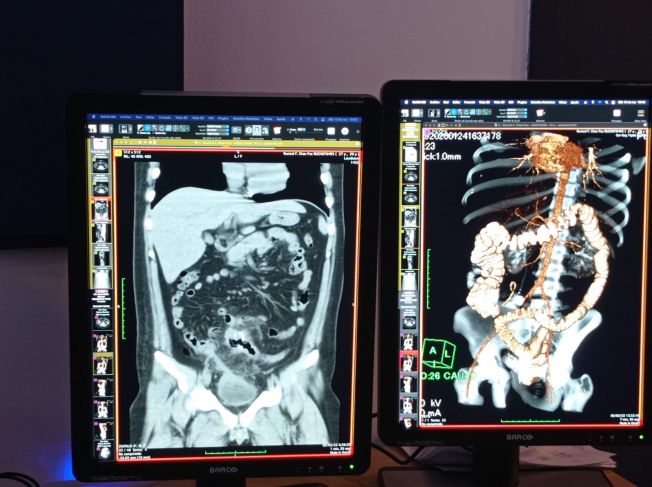

La medicina nuclear es una especialidad en la que se aplica material radiactivo principalmente a pacientes oncológicos, pero también para algunos enfermos del corazón o con problemas como demencias del tipo del Alzheimer o del Parkinson, informó la doctora Gisela Estrada Sánchez, presidenta de la Federación Mexicana de Medicina Nuclear.

La médica participa en el XI Congreso Internacional de Medicina Nuclear y Molecular, que se realiza del 27 de abril al 1 de mayo en Puerto Morelos. En entrevista, explicó que para usar medicina nuclear, específicamente PET/CT (tomografía por emisión de positrones), se ocupa de un acelerador de partículas tipo ciclotrón, de los cuales solamente hay ocho en todo México y uno de ellos está en Quintana Roo, específicamente en el municipio de Benito Juárez.

Aseguró que los avances en medicina nuclear han ayudado muchísimo porque pueden evaluar en un mismo paciente, por ejemplo, los diferentes tratamientos a implementar. El ciclotrón les ha permitido mejores estudios en imagen tomográfica y molecular y dar así una mejor atención médica.